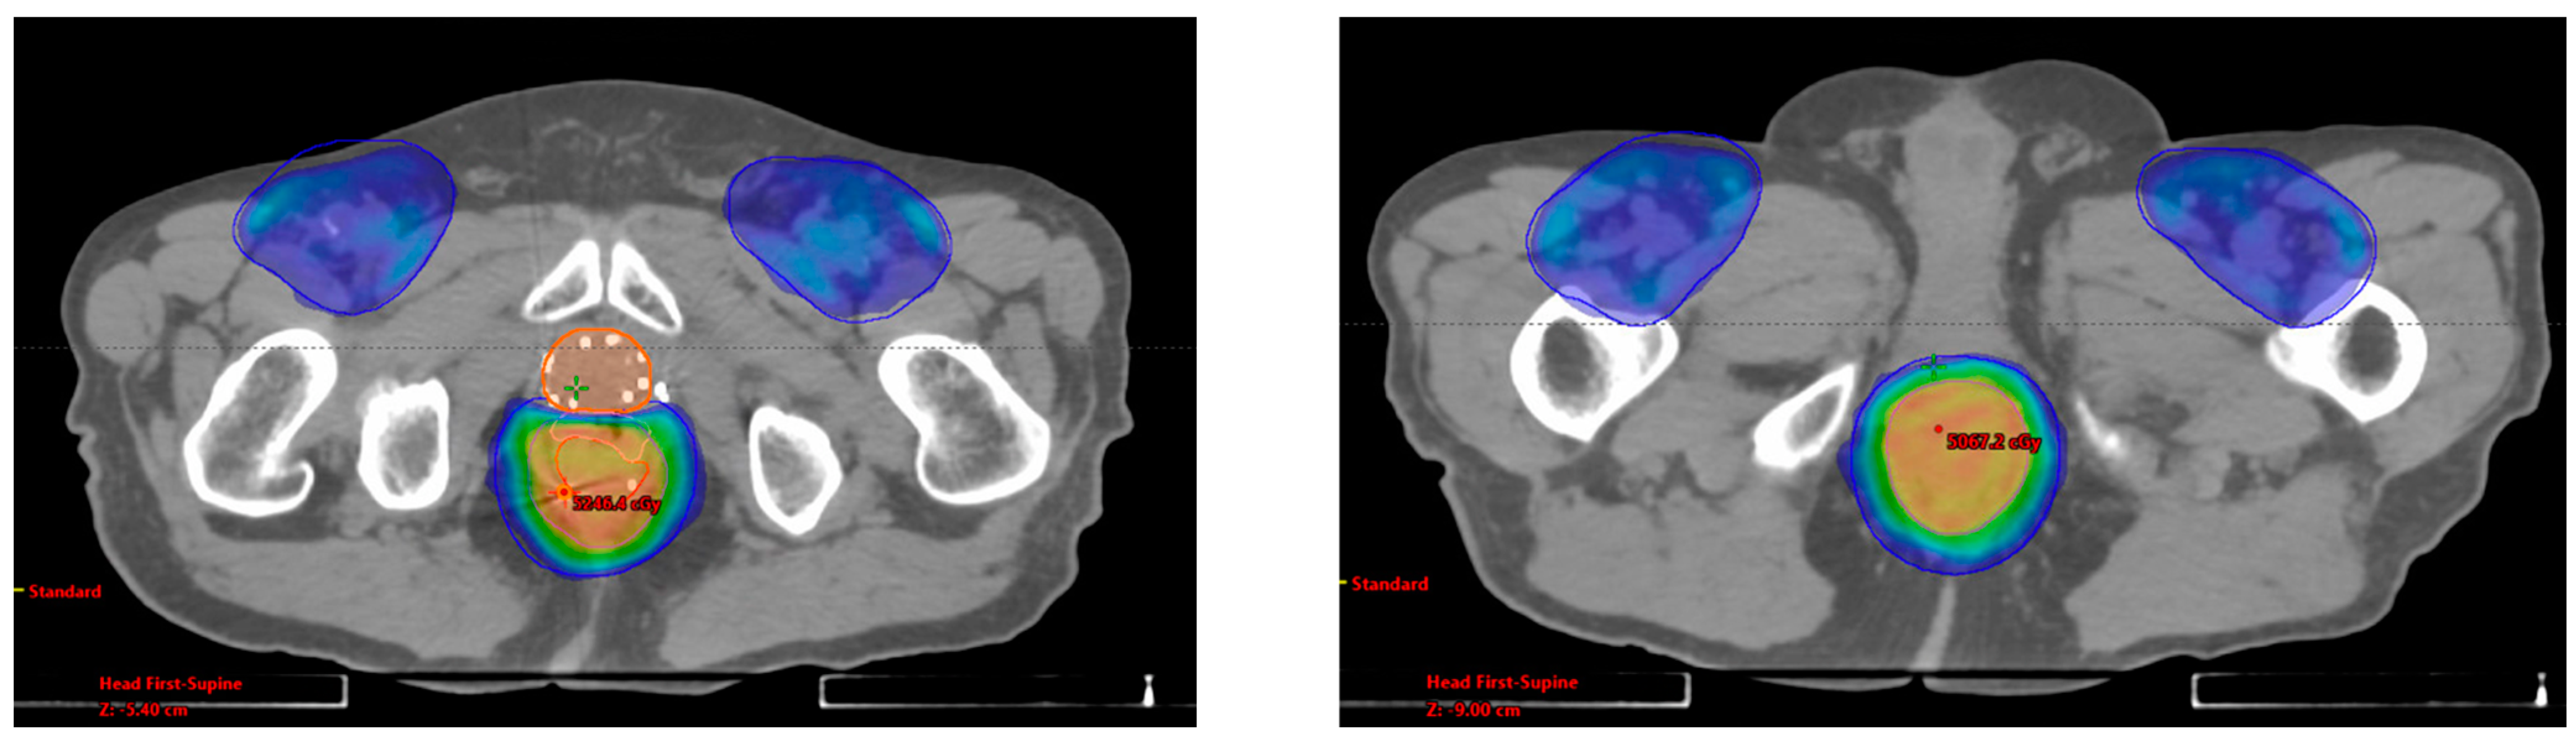

3.2. Case Report 2: Rectal Adenocarcinoma

| Rectal | 2013: -EBRT 81 Gy/45 fx | 2019: -Rectum + LNs 45 Gy/30 fx BID | CR | NED | No POD | No POD | 36 mo |

| Disease | GTV V100% | PTV V100% | Mean Rectal Dose (cGy) | Mean Bladder Dose (cGy) | Max Distance of Spacer (cm) |

|---|---|---|---|---|---|

| Rectal | 62% 1 | 73% 2 | 4462.5 | 3957.6 | 1.10 |